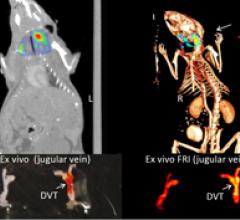

June 7, 2011 — Research presented at the Society of Nuclear Medicine's annual meeting showed a novel optical imaging technique called near-infrared fluorescence (NIRF), which can image dangerous blood clots hiding inside elusive veins. The imaging technique uses light energy with a newly synthesized imaging agent to glean information about cells and tissues. The agent uses a biomarker that seeks out fibrin peptide that is actively involved in the formation of clots.